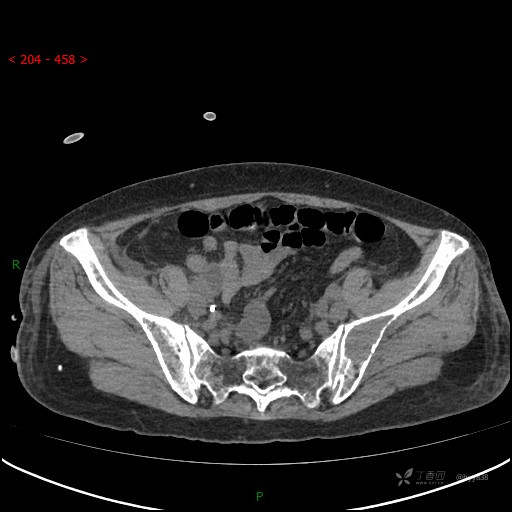

骨窗